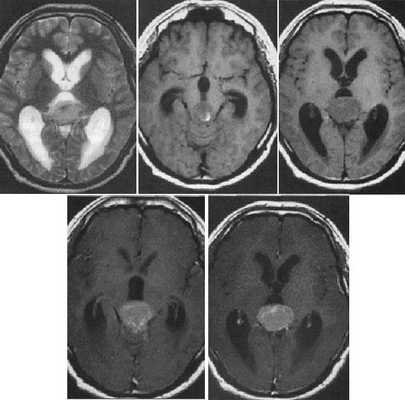

Герминома пинеальной области с метастазированием в хиазмально-селлярную область.

Герминома подкорковых образований слева. Мультикистозного строения опухоль с признаками окклюзии отверстия Монро слева.

Злокачественная смешанная герминативноклеточная опухоль. В боковых желудочках и пинеальной области определяются множественные опухолевые узлы с выраженным перитуморальным отеком. Внутрижелудочковые образования с признаками кровоизлияний. При в/в контрастировании определяется выраженное контрастирование узлов. Дополнительно визуализируется метастазирование по эпендиме боковых и IV желудочков мозга.